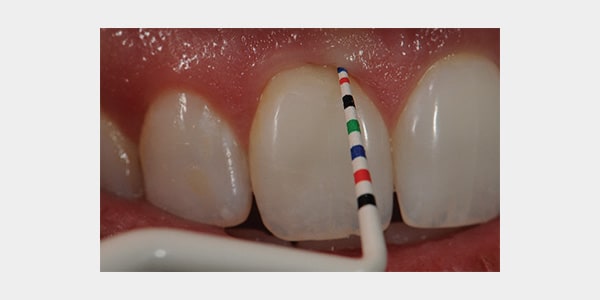

Diagnostic Use: Precise probing can be a challenge due to lack of contrast and visibility. The measurements are typically in 3 mm increments. The new Colorvue probe was designed in 1/2 mm increments and extends up to 3 mm for increased accuracy especially in measuring sulcular depth for margin placement. The use of bright colors to differentiate these measurements makes the probing process much more efficient and accurate.